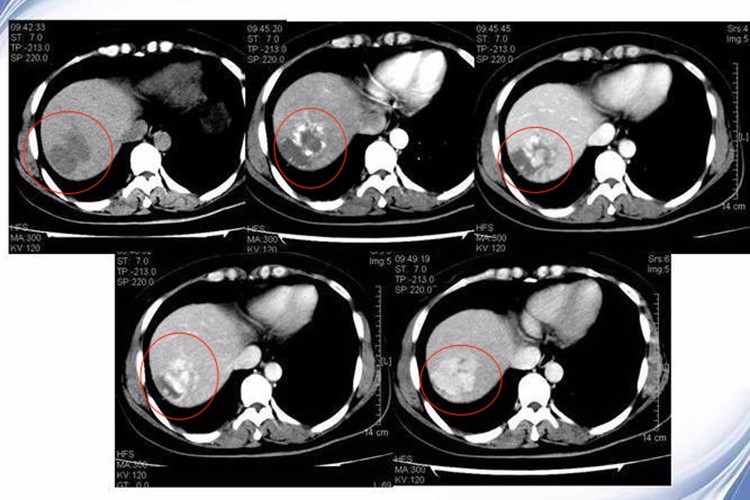

细菌性肝脓肿的肝脏平扫CT呈低密度、不均匀改变,形态多样化,单发或多发,单房或多房,圆形或椭圆形,边界清楚,已形成脓肿者壁较厚,脓肿腔内可有气影。增强的特点为在未形成脓腔前不均匀增强,在形成脓腔后,其壁内侧光滑增强,壁外侧模糊。